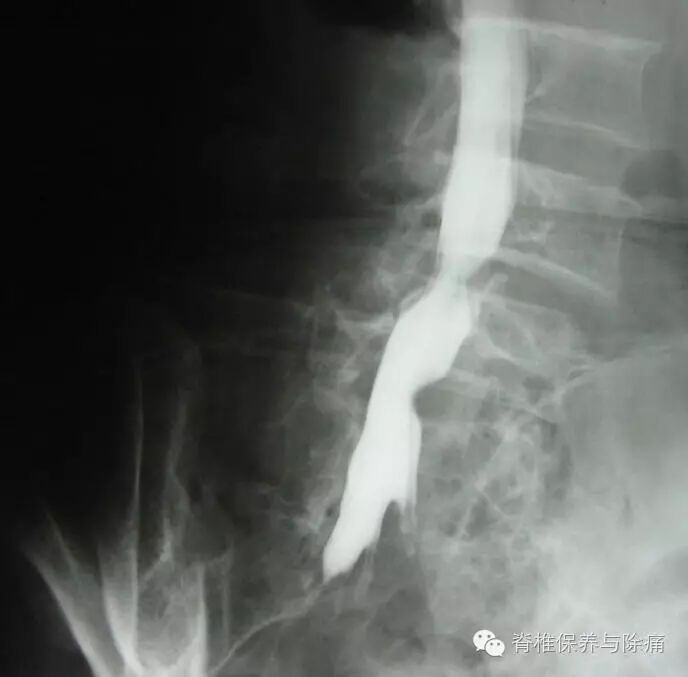

病例1

L4/5椎间盘呈唇样影后突(偏左侧),左侧侧隐窝变窄,硬膜囊外脂肪略受压。